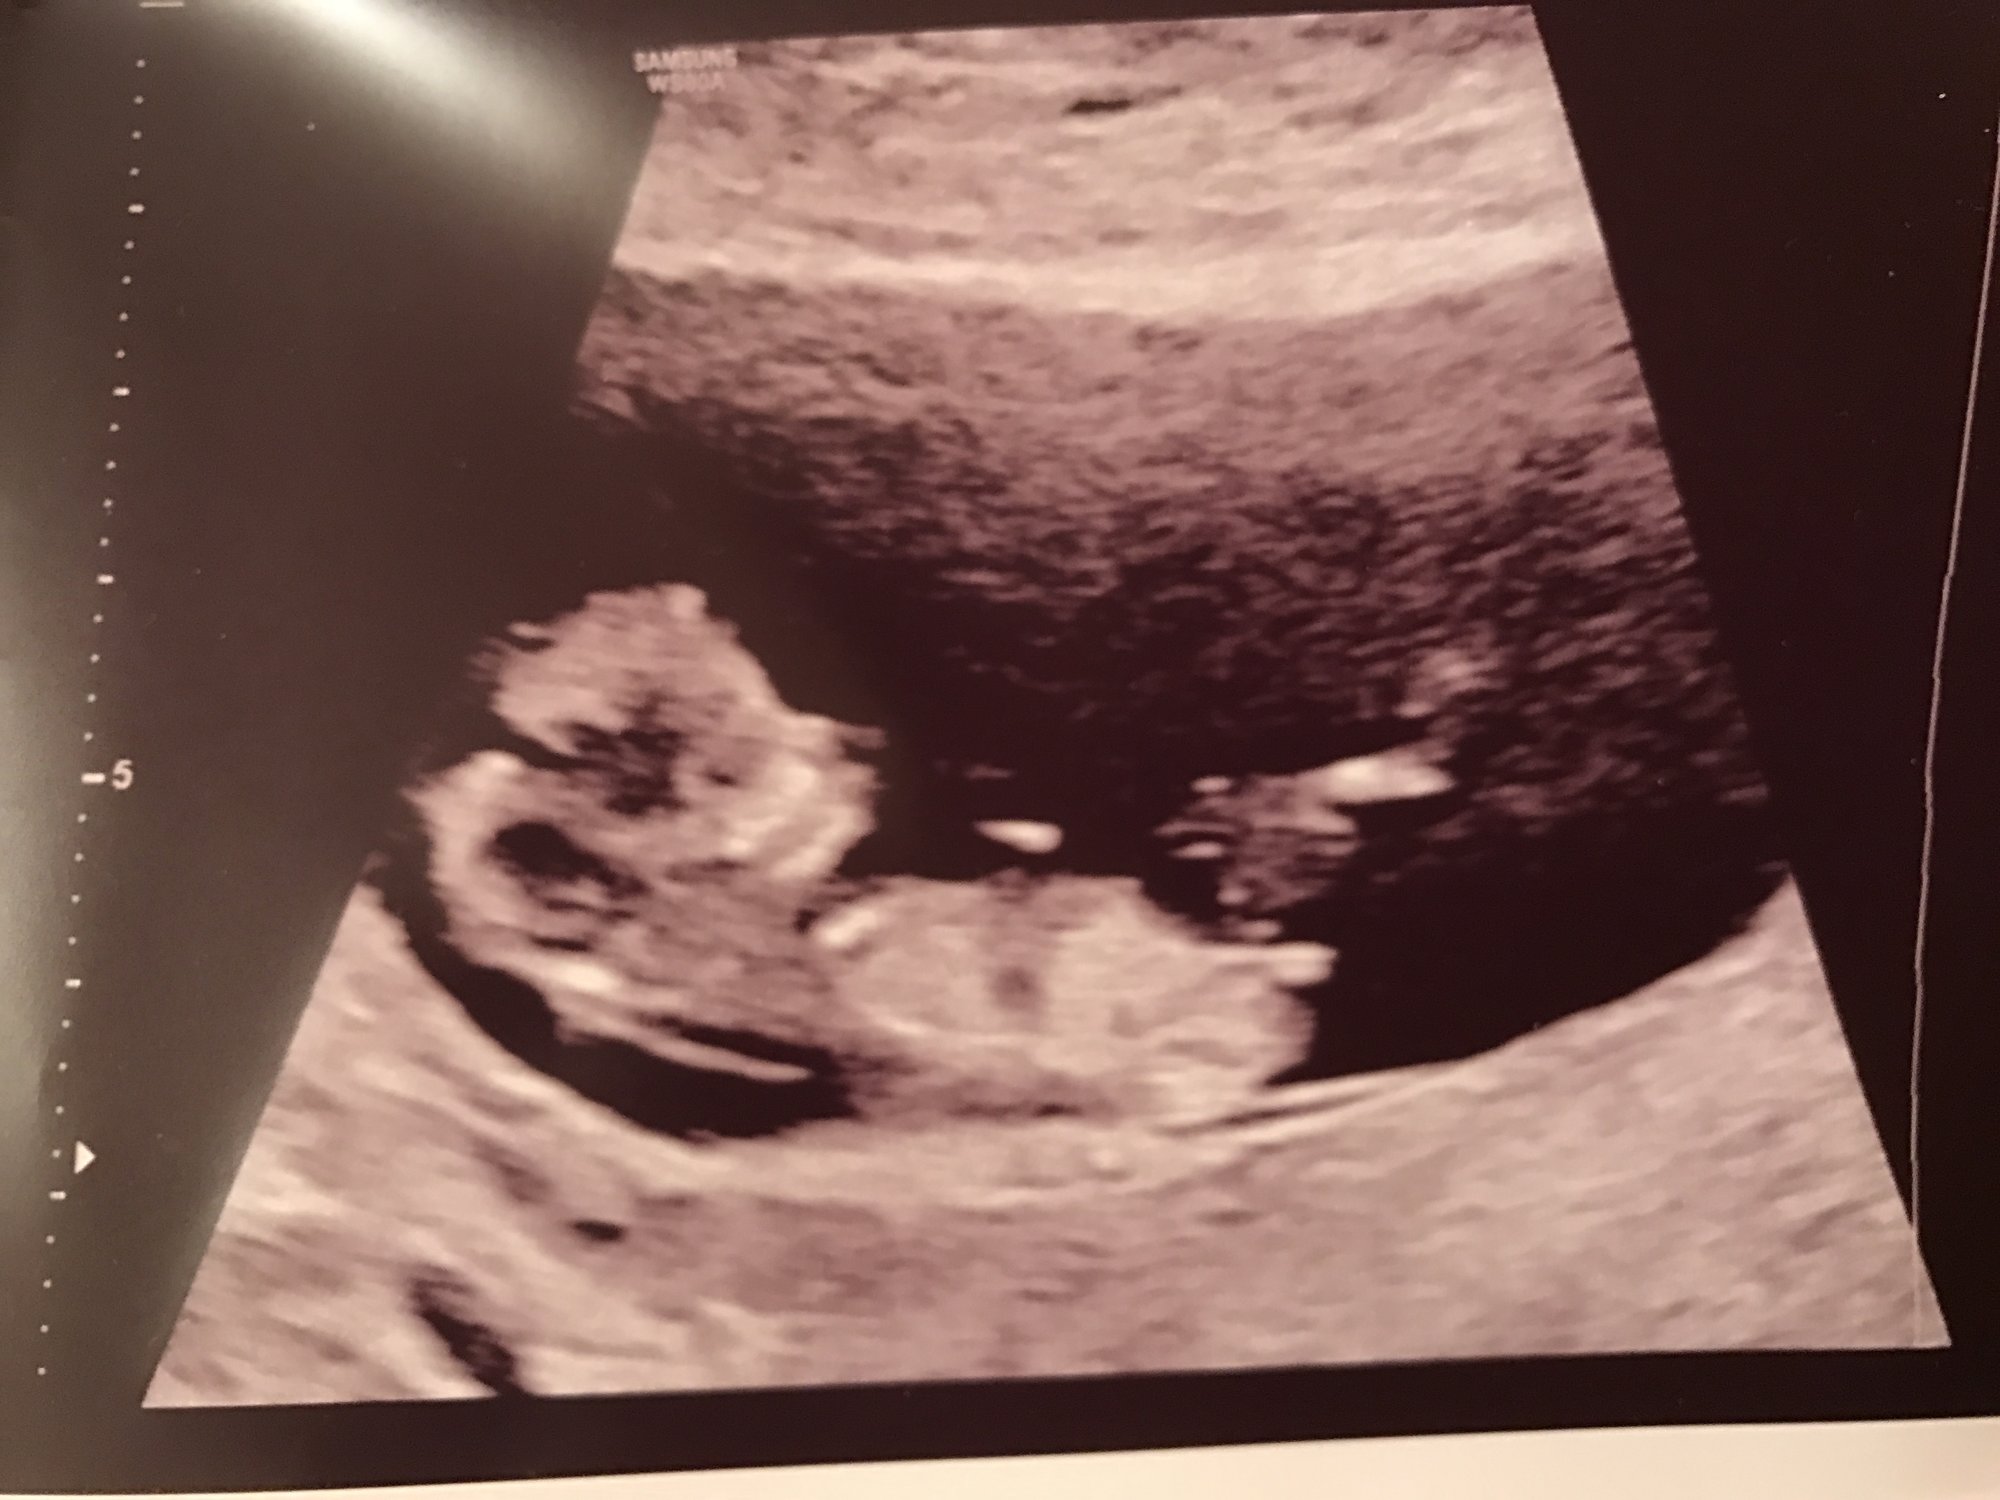

Ultrasound from yesterday at 10weeks 4days. Measuring two days ahead! They did a quick 3D scan and photo! Also finally heard the heartbeat and it was healthy at 171!